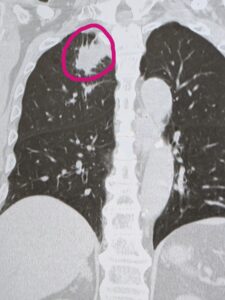

CTをとったところ、右肺に大きな腫瘍を認め、総合病院にご紹介になりました。